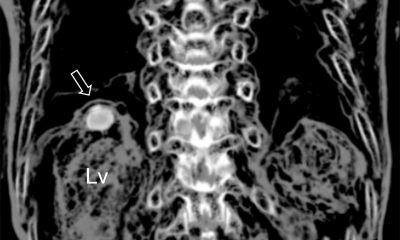

Az orvosok a Baylor Egyetem Dallas volt négy műveletet a méh transzplantáció élődonoros, akik nemcsak a családok, de még csak nem is ismeri a címzettek. Ez az első kísérlet arra, hogy ez a fajta transzplantációs szerint a Time magazin.

Ólom sebész Baylor Egyetem Dr. Giuliano Testa elismerte, hogy a műveletek eredményét, míg kiábrándító, de a jelenléte legalább egy beteg, aki jól érzi magát, azt mutatja, hogy ez a módszer egy nagy kilátás.

méh transzplantációs művelet tartott 10 órán át. Öt órával eltávolítjuk a méhet egy donor testét és ötöt a transzplantáció. A műtéti csapat állt négy sebész Baylor University Medical Center, két sebész Svédország tapasztalatokkal méh transzplantáció, két aneszteziológus és működő hét ápolók.

Nők lesz megfigyelhető a kórházban három hónapig, majd visszatér a normális élet. Ezután az időszak hat hónaptól egy évig abban az esetben sikeres a művelet, a nők végzik az in vitro megtermékenyítés (IVF). Terhes természetesen ezeknek a nőknek nem lehet, mert a petefészkek nem társul az átültetett méh. Mivel a nők kénytelenek folyamatosan veszi mérgező gyógyszerek kilökődését megakadályozzák az átültetett szerv, miután szülni két gyermek, a méh eltávolításra kerül újra.

Hasonló műveleteket végeztek Svédországban, a University Hospital, Göteborg Salgrenska, de a méh donor közeli rokonok. Meg kell jegyezni, hogy a kilenc címzettek transzplantáció után a méh öt nő szült egészséges gyermekek és egyikük terhes, a második alkalommal.